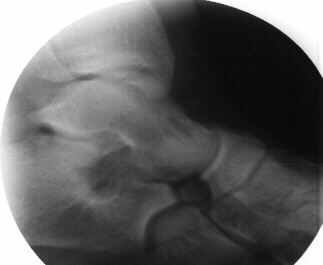

(standing),

oblique,

Harris

views. Tarsal coalition of calcaneonavicular appears to be present. The

subtalar joint does not appear to be involved.

Radiographs - AP, lateral, oblique at 45 degrees, and Harris view. A coalition may be difficult to pick up on the AP and lateral views due to the overlap of bones but there may be some subtle clues. Beaking of the talus or narrowing of the subtalar joint may be present. Calcaneonavicular bony bridges can be seen on the lateral view with the classic "anteater nose" coming from the calcaneous. Harris view may be helpful to evaluate the subtalar joint but a CT is often obtained to rule out subtalar coalition. The ankle may remodel to a ball and socket joint secondary to limited subtalar motion. Coronal CT cuts are most helpful in evaluating talocalcaneal bony bridges while transverse cuts are used for calcaneonavicular bars.